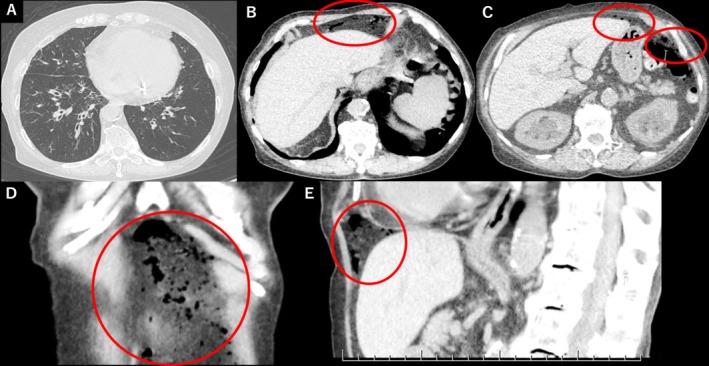

哮喘相关的非手术气腹极为罕见。本病例强调,即使没有腹部症状,自由空气也可能完全由哮喘加重引起,在排除手术原因后,不禁食的保守治疗就足够了。

Asthma-related nonsurgical pneumoperitoneum is extremely rare. This case highlights that even without abdominal symptoms, free air may result solely from asthma exacerbation, and conservative treatment without fasting can be sufficient after surgical causes are excluded.